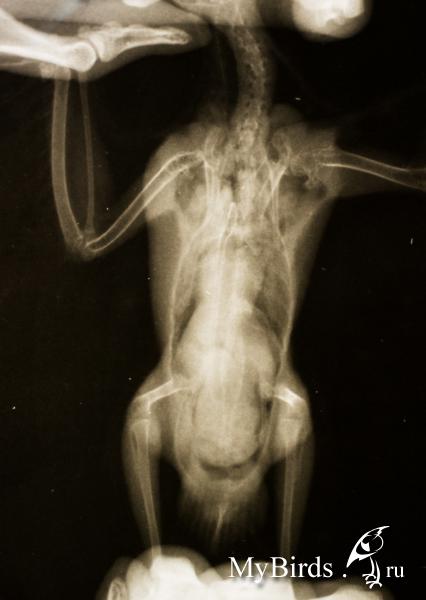

jubi Опубликовано 20 июля, 2015 Автор #25 Опубликовано 20 июля, 2015 снимки лучше наверное на хостинг какой загружать.. но может пойдет размер.буду очень рада и благодарна, если кто-то глянет на снимки..это первый рентген в нашем городе и мы были первой птичкой в практике врача..

jubi Опубликовано 21 июля, 2015 Автор #26 Опубликовано 21 июля, 2015 уважаемые консультанты, гляньте, пожалуйста, на снимки

Violina Опубликовано 21 июля, 2015 #27 Опубликовано 21 июля, 2015 Как ваши дела? По снимку мне что- то затемнение на спине не нравится...Напишите в личку докторам нашего форума с просьбой посмотреть снимки. К сожалению, они не всегда могут просматривать все сообщения...

jubi Опубликовано 22 июля, 2015 Автор #33 Опубликовано 22 июля, 2015 Zosia, спасибо большое за ответ на почту! я вам туда и отвечу. (для форума: или аспергиллез, или микоплазмоз )

Violina Опубликовано 22 июля, 2015 #34 Опубликовано 22 июля, 2015 Ужас... Это вот темная часть на спине и есть патологический процесс? Или в другом месте?

jubi Опубликовано 22 июля, 2015 Автор #35 Опубликовано 22 июля, 2015 (изменено) Это вот темная часть на спине и есть патологический процесс? Или в другом месте? я думаю, что если бы вся темная часть была грибом, то птица бы уже давно не жила и он бы таких размеров вообще не разросся. скорее всего какая-то часть в тех районах. я стараюсь даже не вникать - не моего ума дело.. это дело оставлю профессионалам. завтра сдадим мазок из зева на флору, микоплазму, грибы. договорилась с человеческой лабой. дали палочки и пробирки.надеюсь, получится взять нормально материал. На прямой проекции прекрасно видны гранулемы в верхней части легких,в правом возд.мешке.На боковой- по краю перикарда(тут- или гранулемы. или казеозные слепки типа микоплазмозных). Zosia из предложенных вами препаратов:1) Нурофена нет (есть обычный Ибупрофен)2) Кларитина нет3) Фоспренил и Иммунофан тоже отсутствует.остальное есть. что искать вместо них?4) ЭУФИЛЛИН: р-р инъекц 2.4% или таблетки?5) ДЕРИНАТ: р-р наруж 0.25% или р-р инъекц 1.5%? приступать ли к лечению сразу или обождать результатов посева?начинать все в комплексе или что-то может обождать? Изменено 22 июля, 2015 пользователем jubi